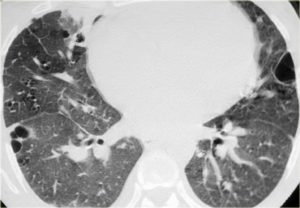

В сомнительных случаях проводят дальнейшие исследования. Компьютерная томография (КТ) с высокой разрешающей способностью выявляет типичные признаки: центролобулярные узелки, окруженные имеющими неправильную форму участками легочной ткани повышенной прозрачности, отражающей обструкцию мелких дыхательных путей. Лучше всего они видны на снимках, сделанных в момент вдоха. Между острыми приступами КТ может не выявить изменений вовсе, или обнаружить малоспецифичные признаки фиброза легких.

Иногда затемнение по типу матового стекла является преобладающим или единственным изменением. Данные затемнения обычно диффузные, но иногда не затрагивают периферические отделы вторичных долек легкого. Локальные зоны повышенной интенсивности, подобные выявляемым при облитерирующем бронхиолите, могут быть основным проявлением у некоторых пациентов (например, мозаичное повышение плотности с задержкой воздуха при КТ на выдохе).